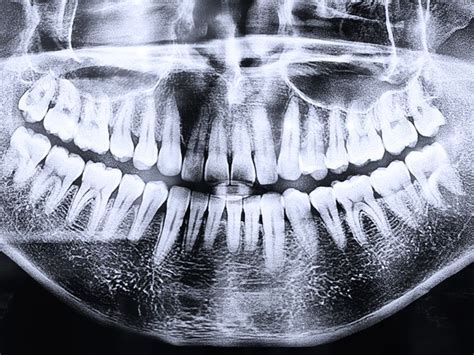

- Ortopantomografía (Panorámicas 2D): También llamada radiografía dental panorámica, es el tipo de radiografía dental más común. Para obtener una panorámica 2D, el paciente se pone de pie o se sienta recto mientras el equipo gira alrededor de su cabeza. Una de las ventajas de las panorámicas 2D es su rapidez. Muestra la totalidad de la estructura facial y mandibular (arcadas superior e inferior, huesos maxilares, mandíbula y estructuras de soporte).